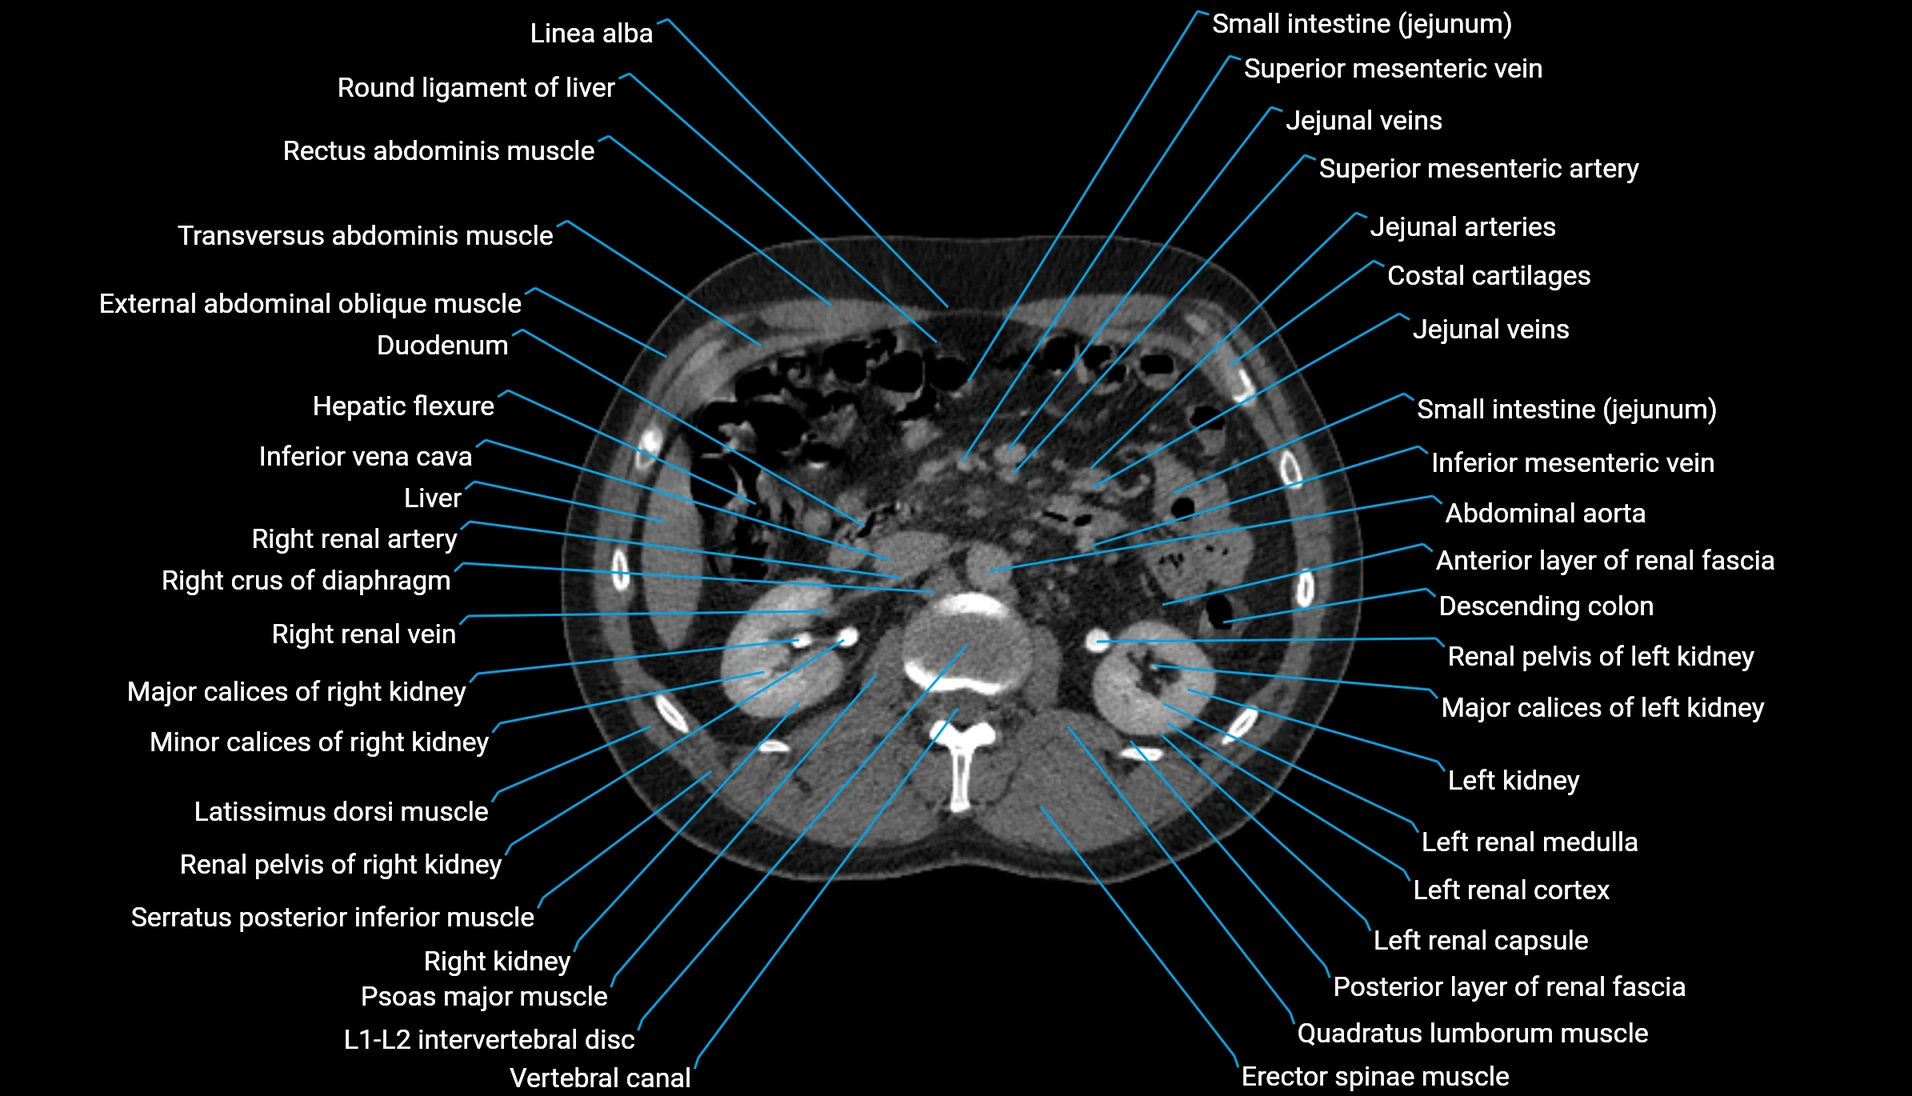

CT Appearance

Non-contrast CT:

-

Demonstrates cortical bone of acetabular rim in excellent detail

Detects fractures, dysplasia, retroversion, or bony overcoverage (pincer impingement)

3D reconstructions used in preoperative hip surgery planning

CT image